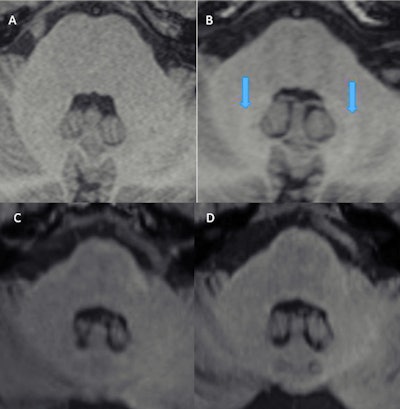

Studies have shown that hyperintensities in the brain are primarily linked to linear nonionic and linear ionic GBCAs. On the other hand, no such link has been found with macrocyclic contrast.

In one study published in 2019 in Investigative Radiology, Radbruch and his team found no accumulations of the macrocyclic type of contrast agent in sheep brains. However, such deposits were clearly found with linear gadolinium. He also cited other studies that showed similar results in other models, such as mice.